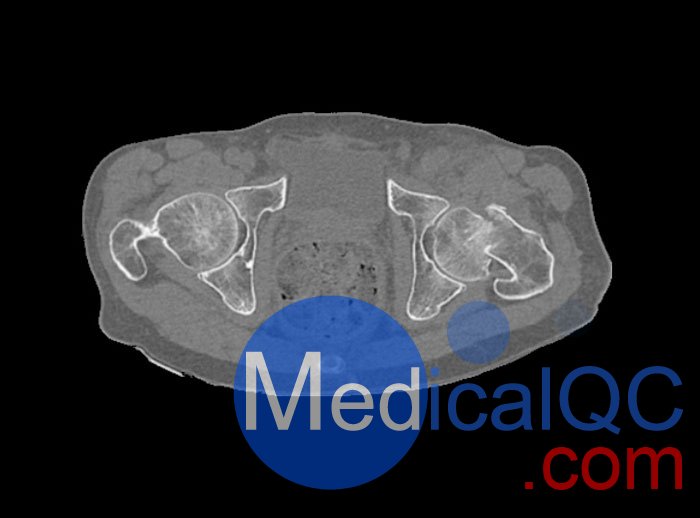

左側(cè)股骨頸移位骨折。

診斷特征

骨骼和軟組織的逼真模擬。

WEK54-01股骨頸骨折骨盆模型,WEK54-01骨盆模體成像效果圖: